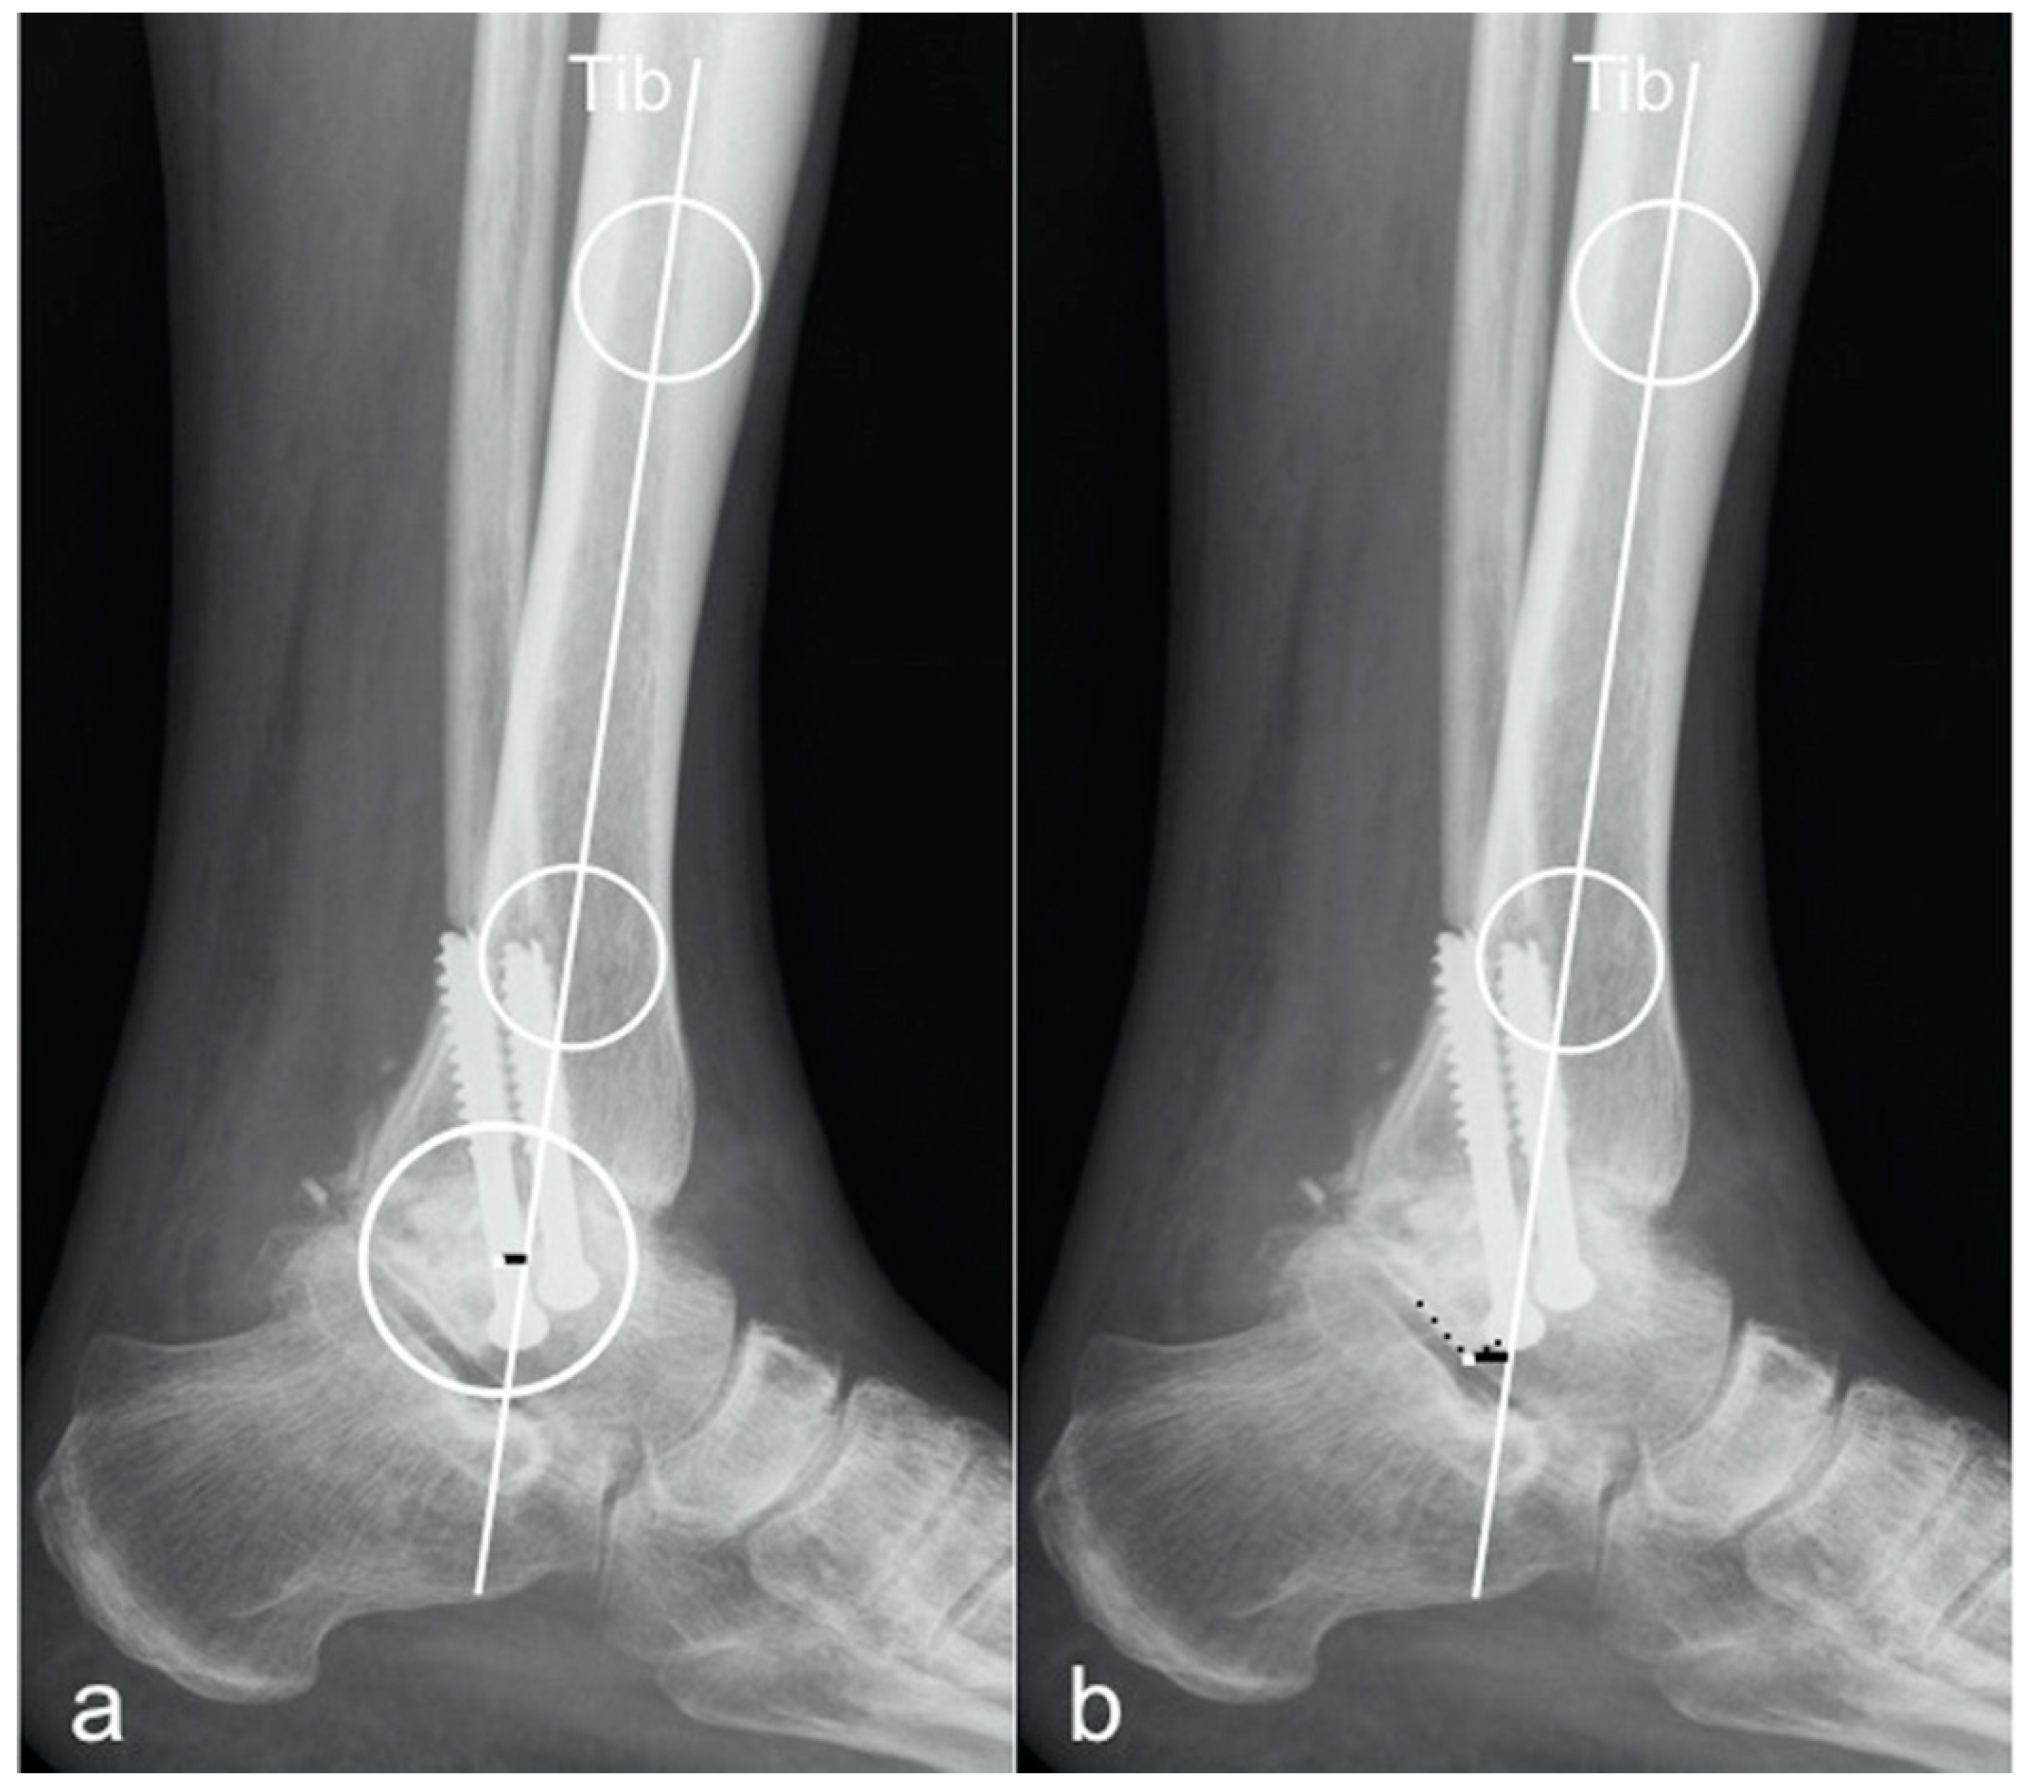

2.1. Radiographic Measurements

- tibCOR:

- procLAT:

- the distance from the tip of the lateral process of the talus to the longitudinal axis of the tibia [9].